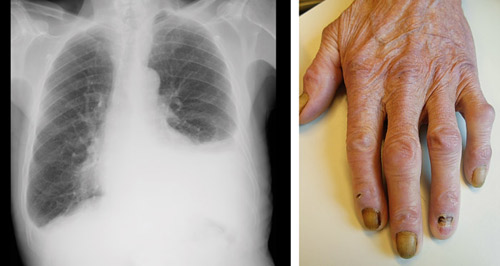

En 80 år gammel mann med kjent røykeutløst kronisk obstruktiv lungesykdom ble innlagt med raskt atrieflimmer, bilaterale ankelødemer og dyspné. Røntgen thorax viste bilateral pleuravæske, mest uttalt på venstre side som initialt ble antatt å være sviktbetinget, men som viste seg å være eksudat. Utredningen ga ingen holdepunkter for infeksjon, lungeemboli, bindevevssykdom, medikamentbivirkning eller malignitet. Ved fornyet klinisk undersøkelse oppdaget man påfallende forandringer på alle fingerneglene.

Gule negler-syndrom (yellow nail syndrome) er en sjelden tilstand med triaden gule negler, lymfødem og respiratoriske symptomer som kan skyldes pleuravæske, bronkiektasier eller sinusitt. Det mest karakteristiske er negleforandringene. Fargen er gul eller gulgrønn, eventuelt begrenset til neglens distale halvpart. Neglene er fortykkede og dyskeratotiske og har tapt den halvmåneformede lunulaen. Det er økt krumning av neglen både på langs og på tvers. Onykolyse kan forekomme. Neglens veksthastighet er betydelig nedsatt, og det er sjelden behov for negleklipping. Oftest er negleforandringene det første symptomet på syndromet, mens pleuravæsken oppstår sist.